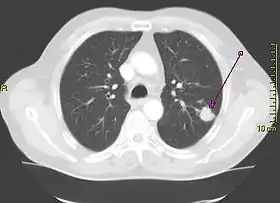

Computed tomography of the chest or chest CT is a group of computed tomography scan protocols used in medical imaging to evaluate the lungs and search for lung disorders.

Contrast agents are sometimes used in CT scans of the chest to accentuate or enhance the differences in radiopacity between vascularized and less vascularized structures, but a standard chest CT scan is usually non-contrasted (i.e. "plain") and relies on different algorithms to produce various series of digitalized images known as view or "window". Modern detail-oriented scans such as high-resolution computed tomography (HRCT) is the gold standard in respiratory medicine and thoracic surgery for investigating disorders of the lung parenchyma (alveoli).

Contrasted CT scans of the chest are usually used to confirm diagnosis of for lung cancer and abscesses, as well as to assess lymph node status at the hila and the mediastinum. CT pulmonary angiogram, which uses time-matched ("phased") protocols to assess the lung perfusion and the patency of great arteries and veins, particularly to look for pulmonary embolism.[1]